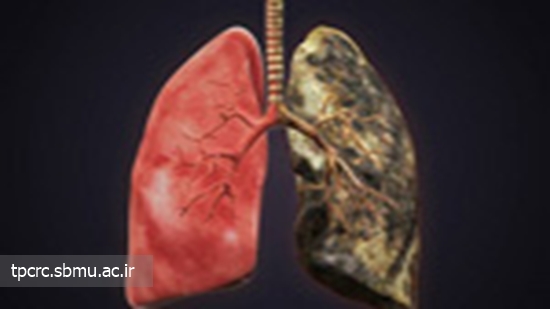

مقایسه ریه سالم و ریه فرد سیگاری

ریه سالم قرمز رنگ است. پس از سیگار کشیدن برای چندین سال، مواد شیمیایی سیگار در ریه ها رسوب کرده و آن را به رنگ سیاه در می آورند. ریه های انسان به عنوان یک فیلتر عمل کرده و از بدن در برابر مواد شیمیایی مضر محافظت می کنند. به جای ورود مواد شیمیایی به مسیرهای هوایی، ریه های شما آنها را جذب می کنند. این مواد شیمیایی می توانند موجب بروز سرطان در ریه شوند.